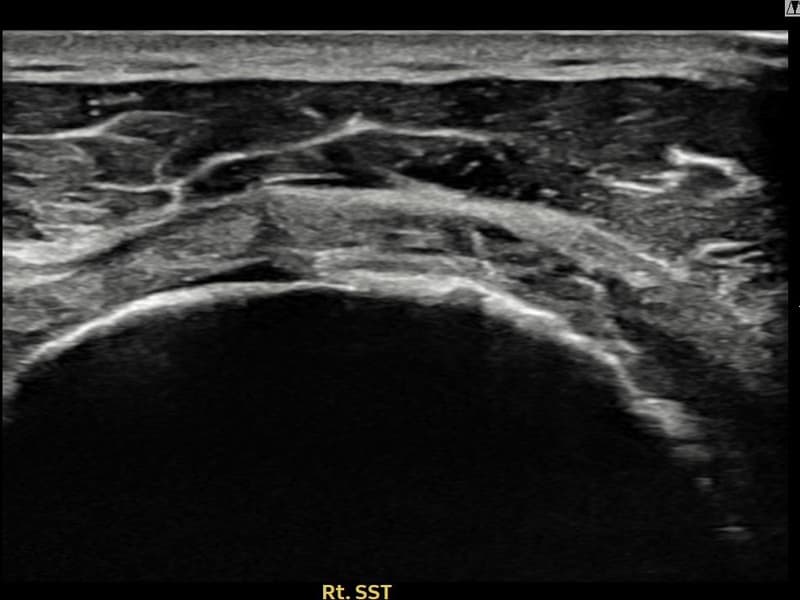

术后

术前超声确认右侧 冈上肌腱 관절면측 광범위 部分撕裂,右侧冈上肌腱回声不连续伴肌腱缺损(16mm × 5mm (肌腱厚度约75%缺损))。术后超声显示撕裂部位充满再生组织,肌腱连续性恢复,回声模式正常化。